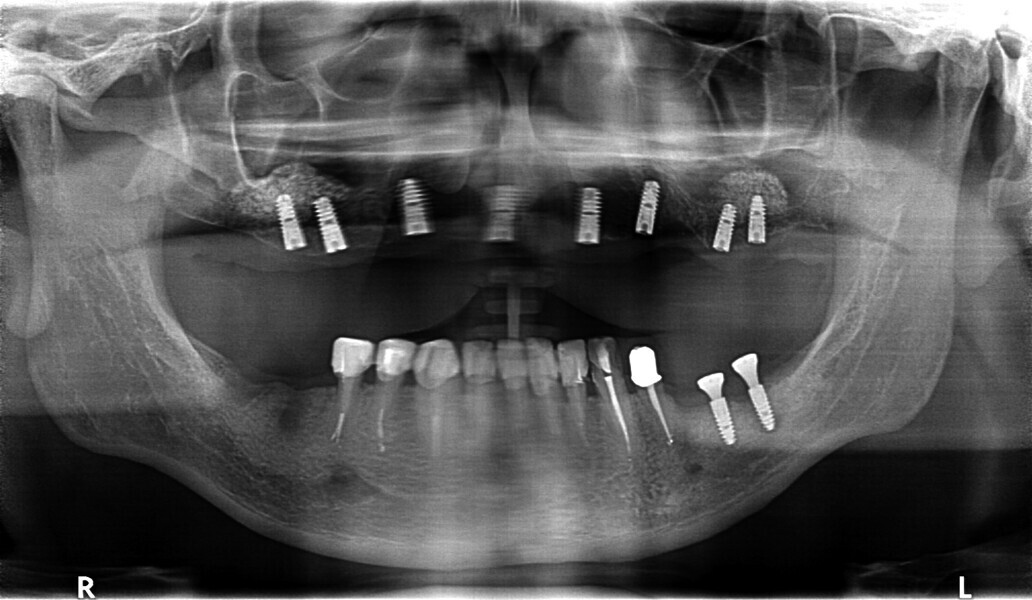

Fig. 29: OPG prior to treatment.